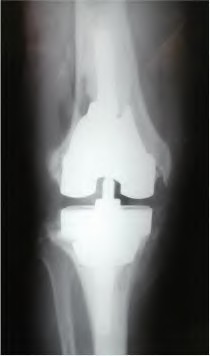

A 64-year-old woman with osteoarthritis underwent bilateral total knee replacement 3 years ago. Current radiographs are shown in Figure A. She reports a 3-month history of bilateral knee pain while at rest and increasing swelling in the knees. Her ESR and CRP are elevated and bilateral knee aspiration cultures reveal Staphylococcus aureus. What is the most likely outcome if the patient undergoes simultaneous, bilateral knee resection arthroplasty with cement spacer and a course of intravenous antibiotics?

This patient presents with bilateral total knee arthroplasty infection.

Wolff et al report Level 4 evidence of 18 patients followed an average of 5 years after bilateral TKA infection. Eleven patients were initially treated with attempts to salvage the original prosthesis (polyethylene l liner exchange, I&D, IV antibiotics and chronic oral suppressive antibiotics. With prosthesis retention, 9/11 (81%) developed recurrent infection at a mean of 15 months. The other 10 patients initially underwent resection arthroplasty with cement spacer and a course of IV antibiotics. Seven of the 10 (70%) underwent reimplantation at a mean of 3 months (6 weeks to 5 months) and none of the patients required revision at mean of two years follow up. Satisfaction rates were significantly higher among this group of patients. The authors advocate the protocol of bilateral TKA resection arthroplasty with cement antibiotic spacer and course of IV antibiotics followed by prosthesis reimplantation.